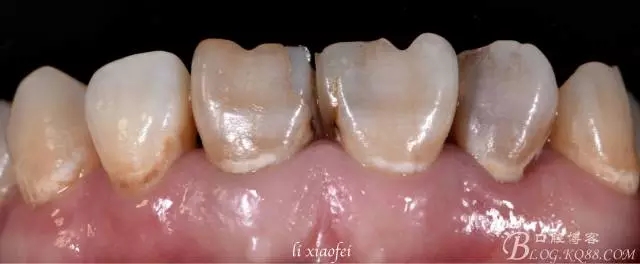

檢查:#11,#21,#22變色;根管治療已經(jīng)完備;#22牙扭轉(zhuǎn);#11、#21近中樹脂充填且有金屬釘輔助固位,樹脂已老化并出現(xiàn)邊緣微滲漏,繼發(fā)齲壞;齦溝:2.5mm,SBI指數(shù)為1,GI指數(shù)為0,#21、#11間GI指數(shù)為1。

e.max鑄瓷是由義獲嘉公司出品,所以比色最好選用義獲嘉匹配比色板。照片可以看出患者患牙色相屬群青、飽和度較高、明度屬暗灰,并且由于是內(nèi)源性著色蛋白酶分解致使牙體有輕微紅染。